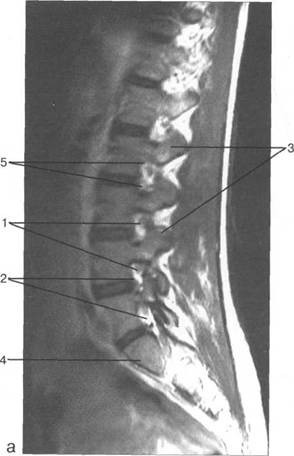

MPT. Cw_v.

MPT.